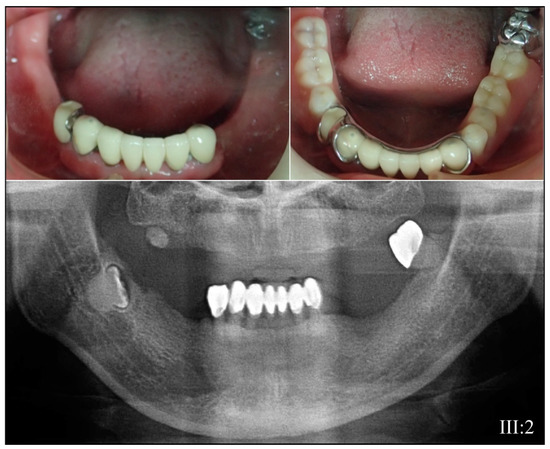

3.3. Eight Families with 3′ DSPP Mutations Causing DD-II or DGI-II

| 3 | Illumina HiSeq 2500 (WES) | NG_011595.1:g.8578T>C; NM_014208.3:c.53T>C; NP_055023.2:p.(Val18Ala) | Missense | III:2, affected mother: 285.78× IV:2, affected child: 189.42× |